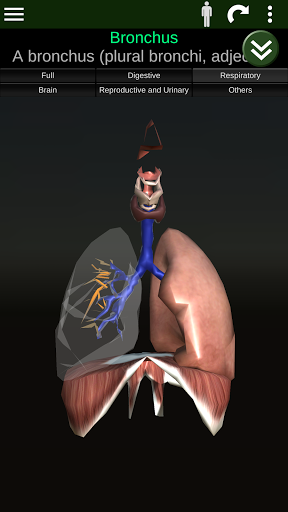

Toont een 3D-anatomisch model van de belangrijkste organen van het menselijk lichaam en een beschrijving van elk orgaan.

* Ademhalingssysteem, inclusief de luchtpijp, bronchiën, longen en een animatie van dit systeem.

* Gemakkelijk te openen en te navigeren (zoom, 3D-rotatie).

* Verberg of toon informatie.

* Beschrijvingen van elk orgel.